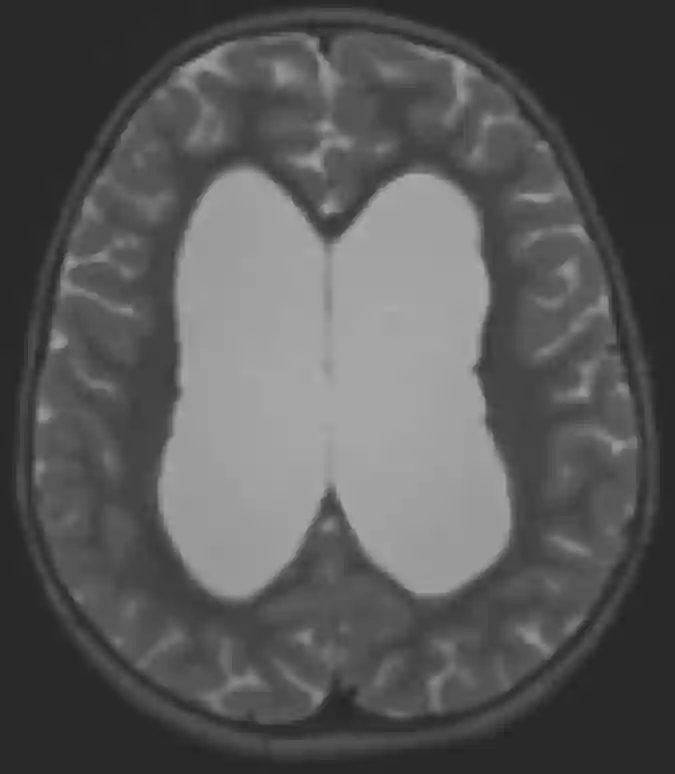

MRI eines Hydrocephalus

Axial T2 gewichtetetes MRI des Schädels mit Erweiterung der Seitenventrikeln.